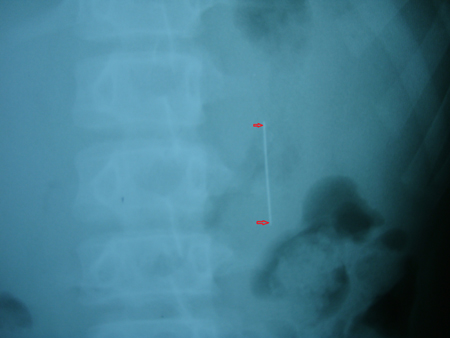

Chiều ngày 21/11, cháu Nguyễn Phan Duy Phước (13 tuổi, trú xã Đăk La, Đắk Hà, Kon Tum) trong lúc vừa kết vòng hoa vừa ngậm chiếc kim khâu dài 6cm, do vừa làm vừa nói chuyện nên Phước đã nuốt phải chiếc kim vào dạ dày. Ngay lập tức, Phước được gia đình đưa vào nhập viện ĐK Kon Tum.

Kết quả chụp X Quang cho thấy, chiếc kim may dài 6cm nằm dọc trong dạ dày cháu Phước. Do dị vật là chiếc kim dài, sắc nhọn nên diễn biến rất khó lường, có thể có nhiều biến chứng.

Nên để đưa dị vật ra ngoài, các bác sĩ quyết định áp dụng biện pháp hướng dẫn cho bệnh nhân ăn nhiều chất xơ sẽ khiến cho phân chắc lại, từng bước “dìu” chiếc kim ra ngoài theo đường bài tiết, hạn chế tai biến.

Tuy vậy, các bác sĩ vẫn luôn sẵn sang để mổ cho bệnh nhân nếu dị vật di chuyển không như ý đồ ban đầu.

Sau một thời gian kiên trì với liệu pháp ban đầu, cuối cùng chiếc kim đã di chuyển dọc theo thành ruột non và được thải an toàn ra ngoài.